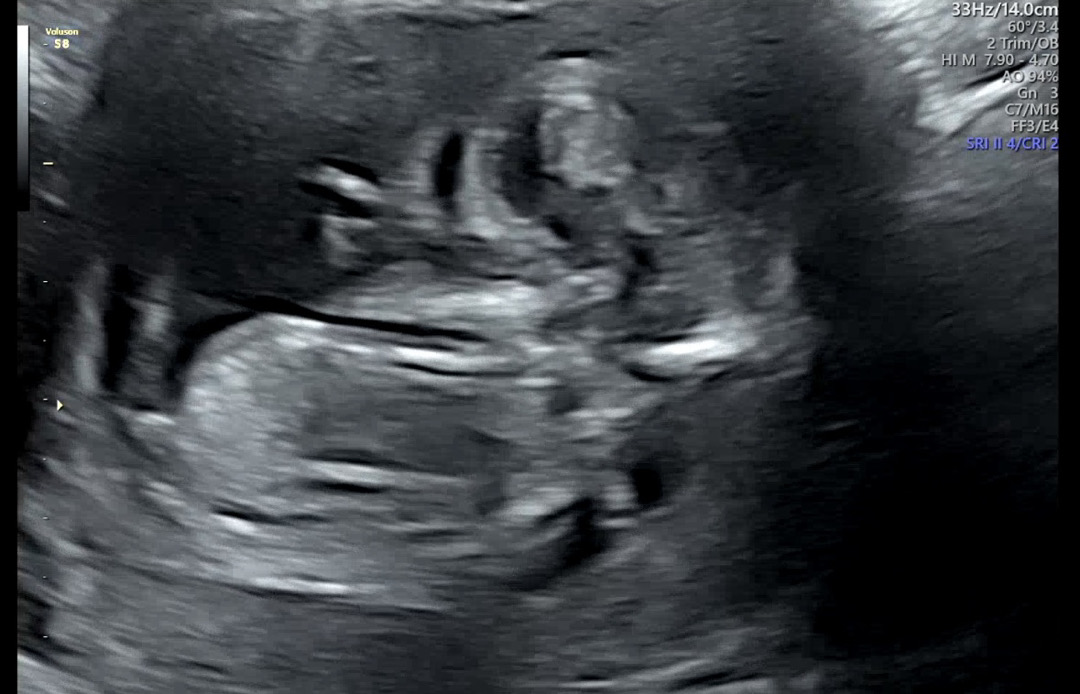

각도법 한번 같이 봐주세요 ㅎㅎ

이 사진은 보이실까요 ㅎㅎㅎㅎ

머리랑 엉덩이 구분이 안갈정도로 너무 선명하지 않아요 ㅠ 다른 사진 없나요